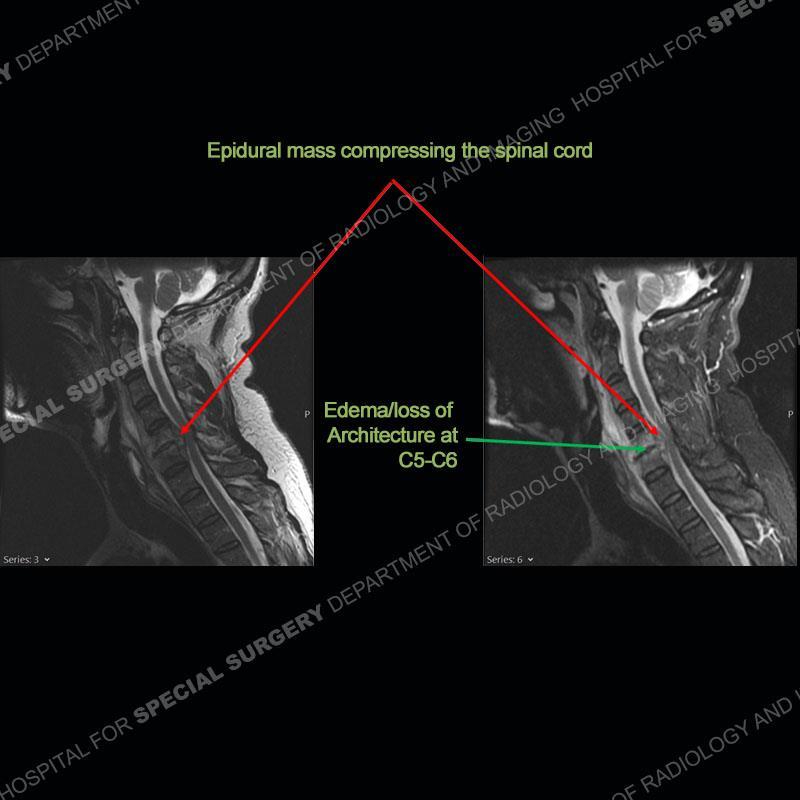

The radiographs demonstrate a prevertebral soft tissue fullness centered at C5-C6 that persists even on extension. There is a slight loss of disc height at C5-C6. The CT more readily shows the prevertebral soft tissue swelling at C5C6 where there is a punctate focus of gas. On the MRI, there is a marked amount of edema and a heterogeneous collection in the prevertebral soft tissue at C5-C6. Edema is present of the C5 and C6 vertebral bodies with a loss of the normal architecture about the disc space. A heterogeneous epidural collection has formed that causes compression of the spinal cord asymmetric to the left side and also precipitates severe left sided neural foraminal stenosis.

Diagnosis: Spontaneous Retropharyngeal Abscess (RPA) with Discitis/Osteomyelitis, Epidural Abscess, and Cord Compression

Spontaneous RPA in the non-immunocompromised, adult population is an extremely rare occurrence. RPA most frequently occurs in young children and most typically after a URI. It may be associated with torticollis in Grisel syndrome. In the adult population, the pathomechanism is not well understood with some suggesting a hematogenous spread or perhaps a seeding from the adjacent aerodigestive tract. The abscess as in this case can extend to involve the vertebral column and then the neural elements. At times, this process can be treated with antibiotic therapy alone but when there are neurologic symptoms and especially progression of neurologic symptoms, surgical intervention is warranted. In this case, given the extent of the process and the patient’s clinical situation, a corpectomy with fusion was performed in addition to antibiotics.